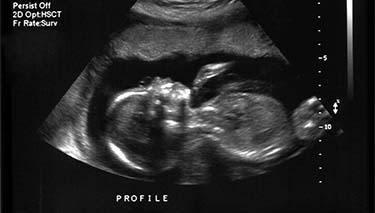

Many parents are amazed by the amount of detail they can see at the 12 week ultrasound. They are also surprised by their foetus's movements and agility. Of course, at 12 weeks gestation it is too early for a pregnant mother to be aware of her baby moving. And it can be a strange sensation when looking at the monitor and seeing movement but not being able to physically detect it.

Many parents feel an instant emotional connection with their baby when they see it for the first time. It's not uncommon for partners to say that until the 12 week ultrasound, the whole pregnancy idea was a little foreign and somehow not real. But being able to see their baby rather than talking about it and having to use their imagination, can make all the difference.